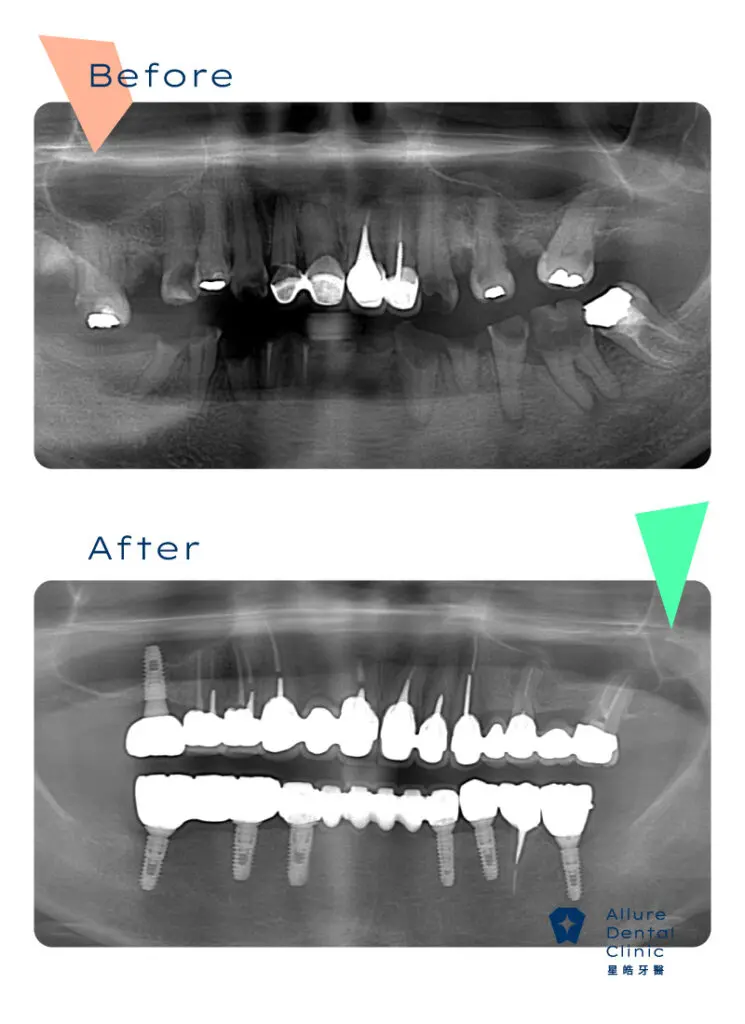

全口重建案例3

主治醫師:副院長 林禹書 醫師